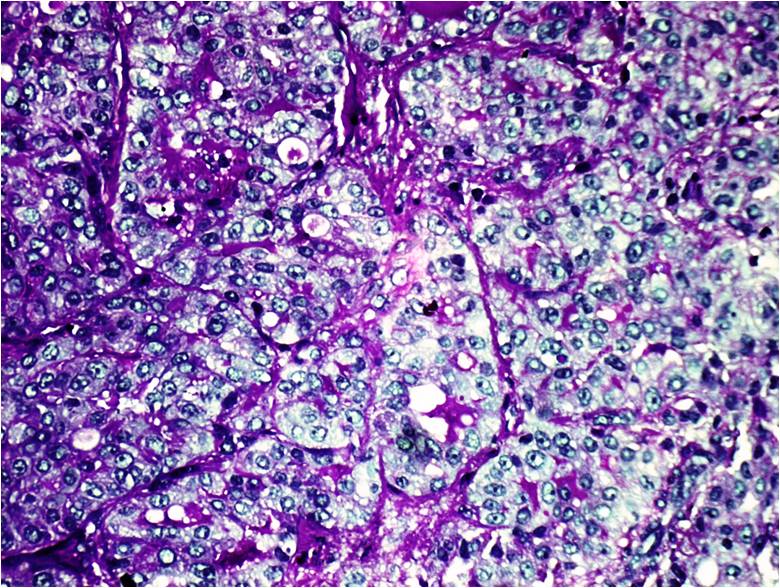

Secretory carcinoma is a rare low grade malignant breast carcinoma of children and adults. Since patients are often young and presents with indolent breast lump in the breast, a high degree of suspicion is often needed for the clinical diagnosis. Fine needle aspiration cytology (FNAC) is often the primary investigation, and because of the indolent clinical presentation, rarity of tumour and unanticipated cytological findings a primary cytological diagnosis of secretory carcinoma is often difficult.We present a case of 13-year-old female, presented with a well defined mobile right breast lump. The aspiration cytology revealed highly cellular smears consisted of singly scattered and loosely cohesive cluster of monomorphic cell population of round to ovoid cells with bland cytological appearance in background of thick mucinous material, leading to cytological diagnosis of secretory carcinoma. A primary diagnosis of secretory carcinoma on FNAC can provide early and definite surgical management including simple mastectomy with axillary lymph node resection recommended for treatment of secretory carcinoma.References